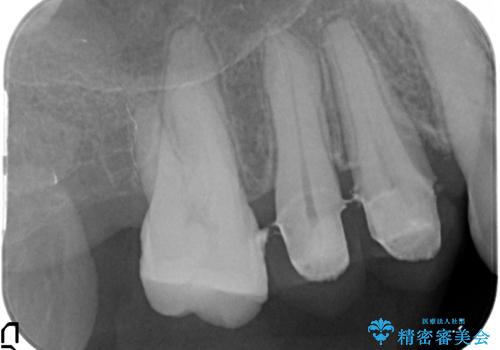

検査の結果、強い歯ぎしりによる歯の周囲の骨の吸収が認められたため歯槽骨の再生・歯周ポケットの除去・力に対抗する連結補綴・補綴前処置としての小矯正を計画します。

特定の歯に強く力がかかりまた歯周病により臨床歯根が短くなっているような場合、歯の動揺を抑えるため連結補綴が検討されます。

歯の動揺が続くとより周囲の骨を失い最終的には歯を喪失してしまう可能性が高くなってしまうためです。

今回連結補綴を行うにあたり、歯周病の問題を解決するために再生療法・歯周ポケット除去手術を、またより歯の神経を保存し力に対抗できる環境を整えるために小矯正を行い精度の高いメタルボンドクラウンを製作することができました。